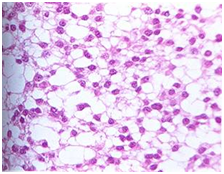

根据肿瘤的组织学特点,星形细胞瘤可分为纤维型、原浆型、肥胖细胞型等类型。下面是在显微镜下的常见的星形细胞瘤分型。

纤维性星形细胞瘤 原浆性星形细胞瘤